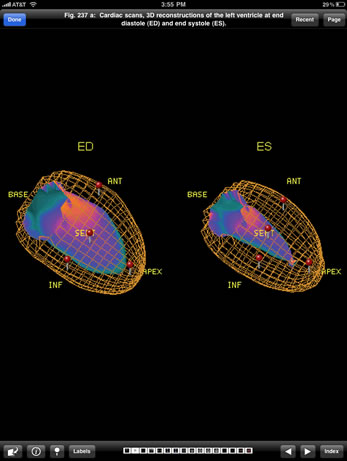

The Imaging Atlas of Human Anatomy, 4th edition, presents a healthy human body as seen via the full range of modern imaging techniques. Content includes images showing cross-sectional views in CT and MRI, nuclear medicine imaging, and more.

Based on the print atlas, written by Jamie Weir, Peter Abrahams, Jonathan D. Spratt, and Lonie Salkowski, this content collection offers a complete view of the structures and relationships within the body through a variety of imaging modalities.